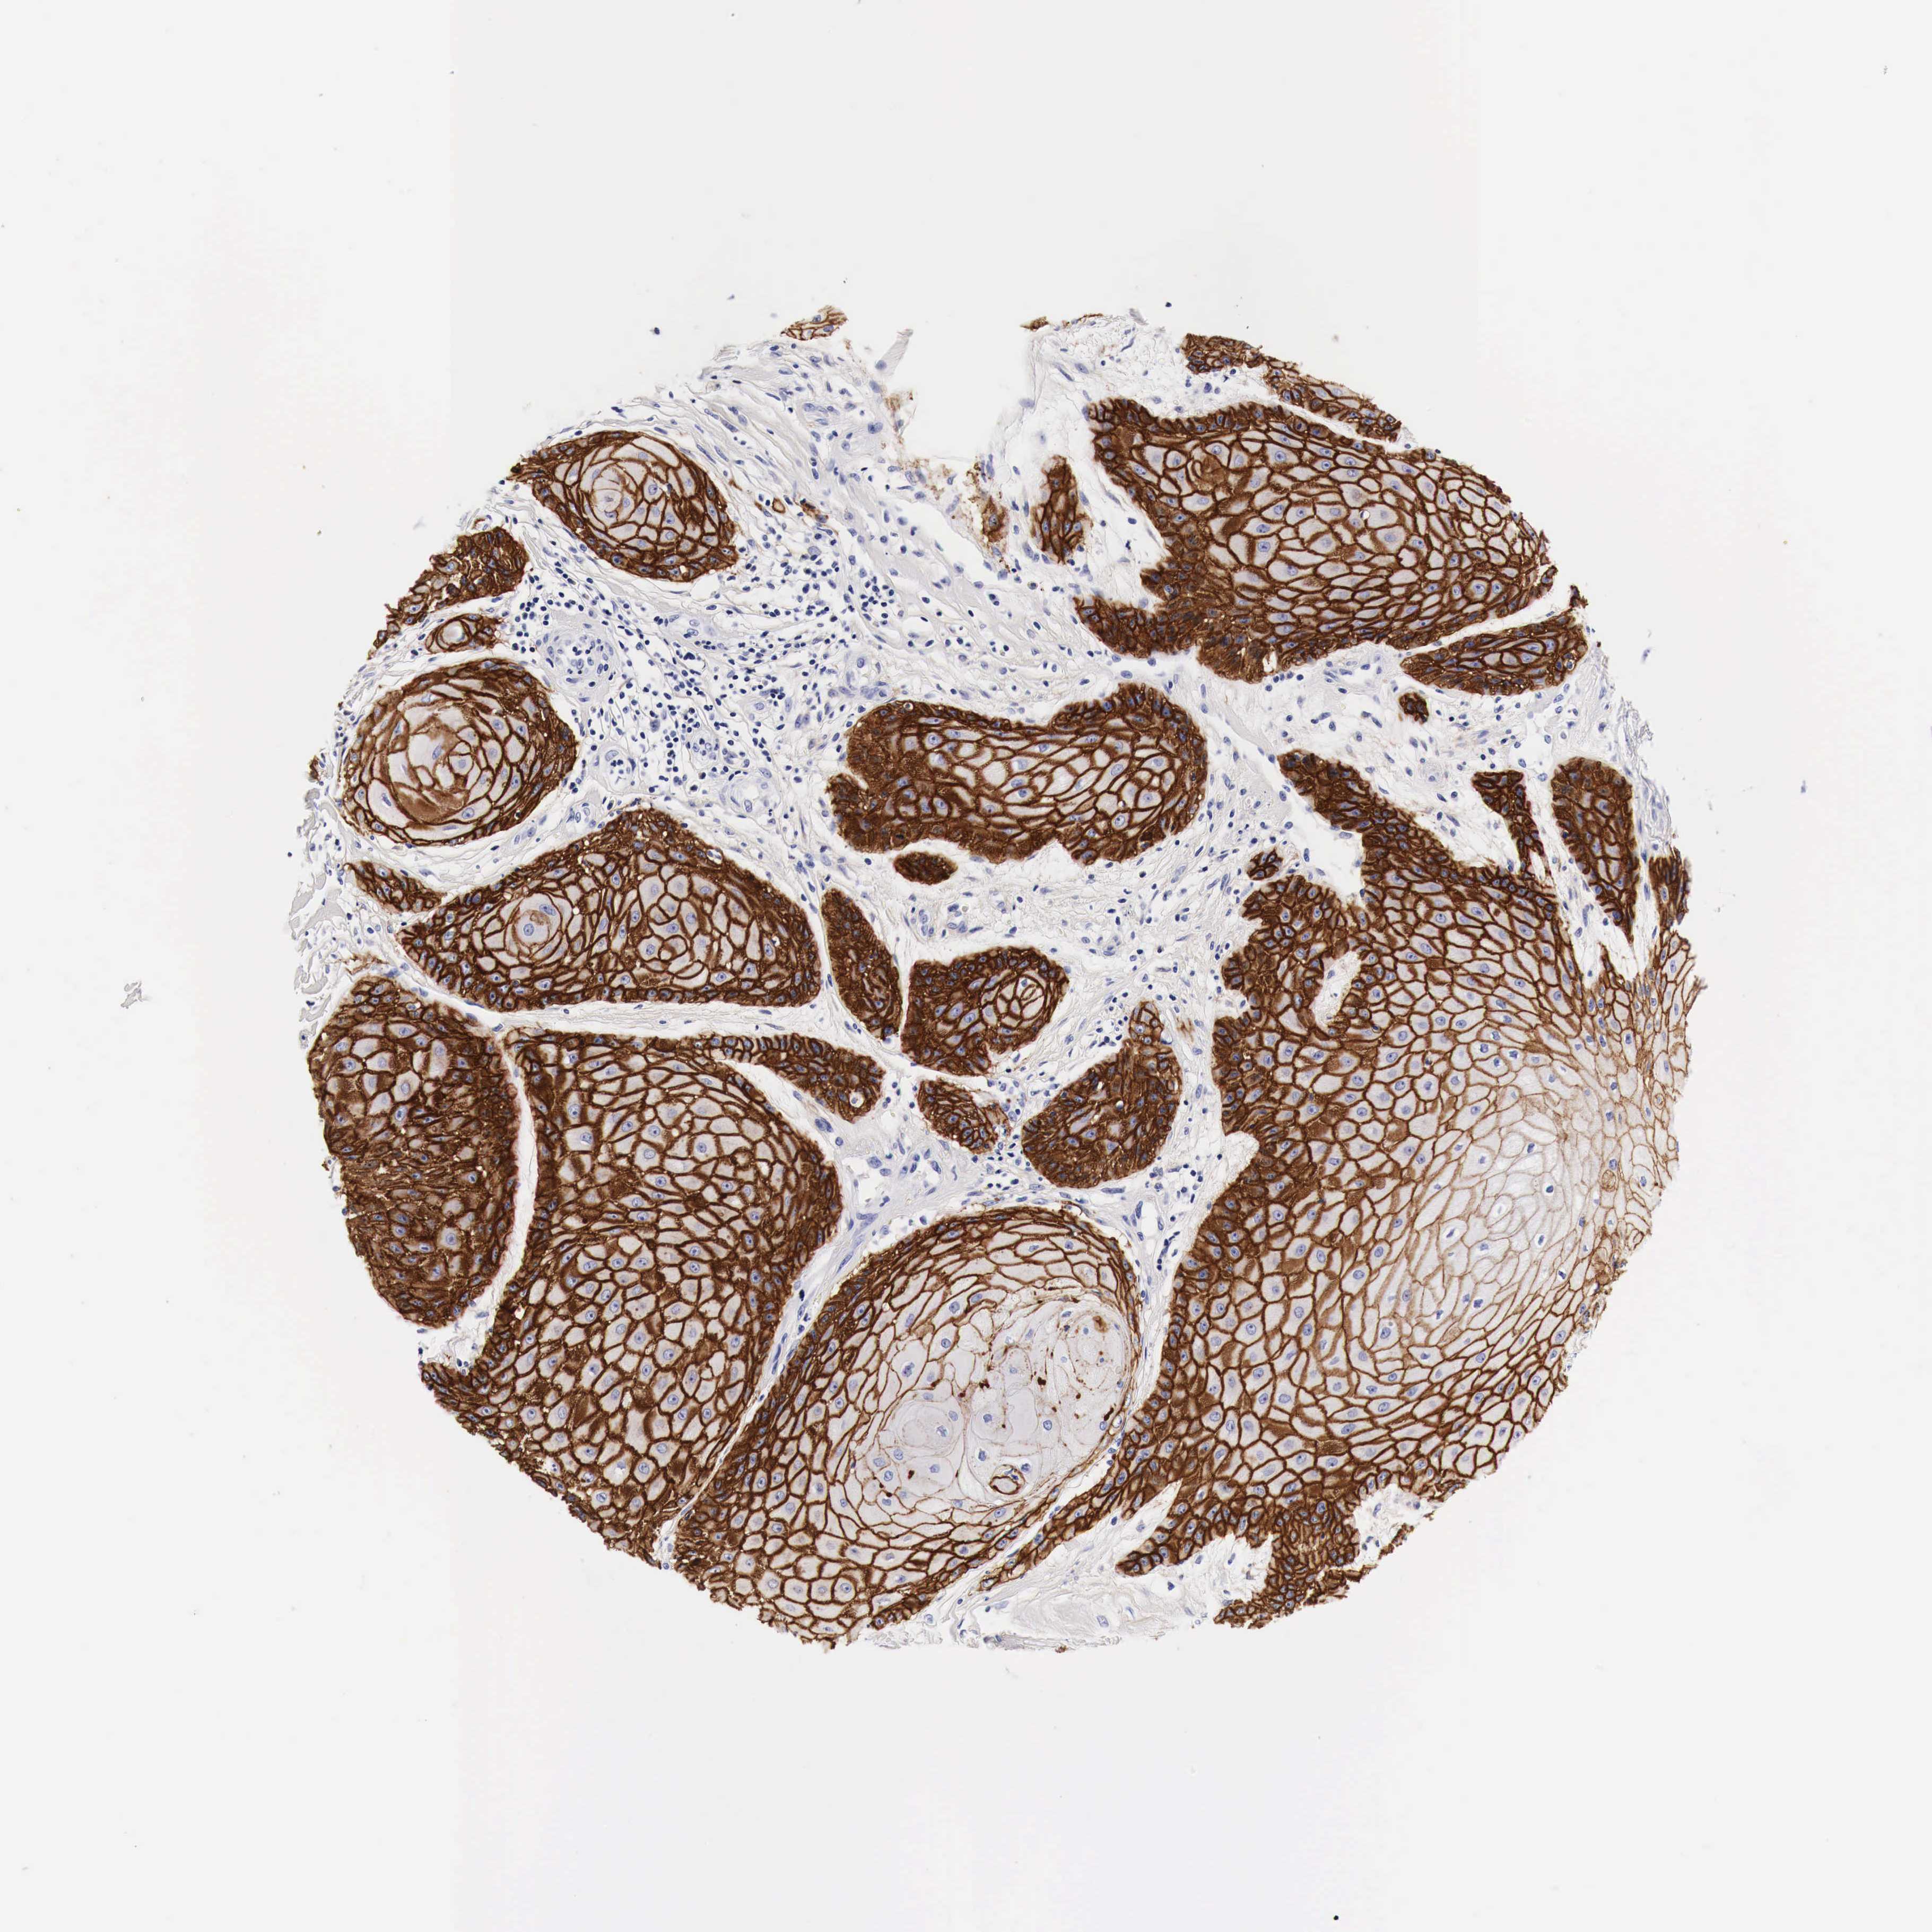

CANCER SKIN CANCER Show tissue menu

SKIN CANCER - Protein expressioni

A mouse-over function shows sample information and annotation data. Click on an image to view it in a full screen mode. Samples can be filtered based on level of antibody staining by selecting one or several of the following categories: high, medium, low and not detected. The assay and annotation is described here.

Each image is clickable and will lead to virtual microscopy that enables deeper exploration of all samples and also displays staining intensity scores, fraction scores and subcellular localization as well as patient and tissue information for each sample.

Squamous cell carcinoma, NOS